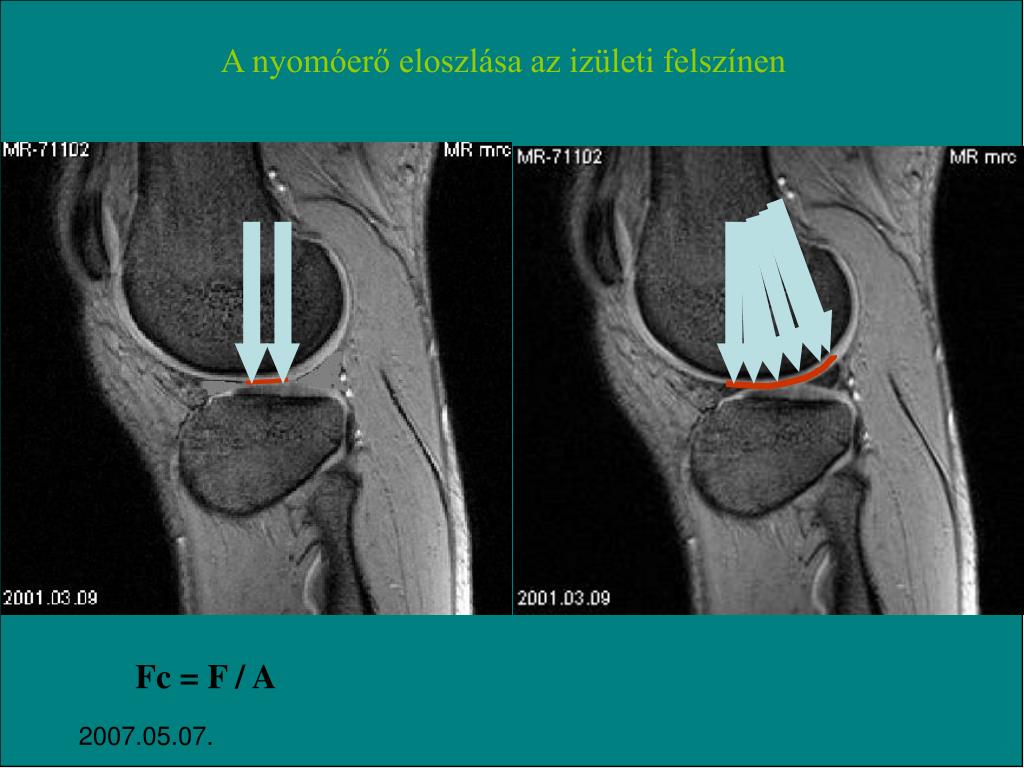

17. A nyomóerő eloszlása az izületi felszínen Fc = F / A 2007.05.07.